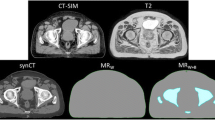

MRI sequences were converted to sCT using a hybrid atlas-voxel method as described in Dowling et al. [11], with the converted Fast SPACE (F-sCT) compared to the Standard SPACE (S-sCT) conversion. Mean Absolute Error (MAE) for HU for the entire body, along with tissue and bones only was calculated by comparing the F-sCT to the S-sCT with the auto-segmented body and bone masks from the S-sCT. An anatomical comparison of the body and bone volumes between the generated sCT was completed considering volume differences, mean Hausdorff distance and Dice Similarity Coefficient (DSC) comparison.

The Fast sequence scan was able to be completed on all patients with no modifications required by the system. This sequence was able to be converted to sCT as per Dowling et al. [11], with no additional artefacts seen in qualitative review of the fast MRI sequence scan or converted F-sCT. An example of the standard MRI and fast MRI, as well as the corresponding S-sCT and F-sCT can be seen in Fig. 1.

The mean absolute error (MAE) in HU over the ten patients for the F-sCT compared to the S-sCT with the body and bone masks from the S-sCT, in addition to tissue only, is shown in Fig. 2. The average MAE for the body was 14.98 ± 2.35 HU, for tissue only was 12.68 ± 2.75 HU, and for the bone was 40.77 ± 5.51 HU.

The volume percentage difference, mean Hausdorff distance and DSC results for both the body and bone contour comparison can be seen in Table 2. The average body volume difference was 1.57% ± 1.65%, whilst the average bone volume difference was − 0.69% ± 2.42%. The mean Hausdorff value was less than 2 mm for both the body and bone volumes, with the body contour comparison producing a DSC of at least 0.976, and an average of 0.985 ± 0.004, and the bone contour producing a DSC of at least 0.907, and an average of 0.950 ± 0.018.